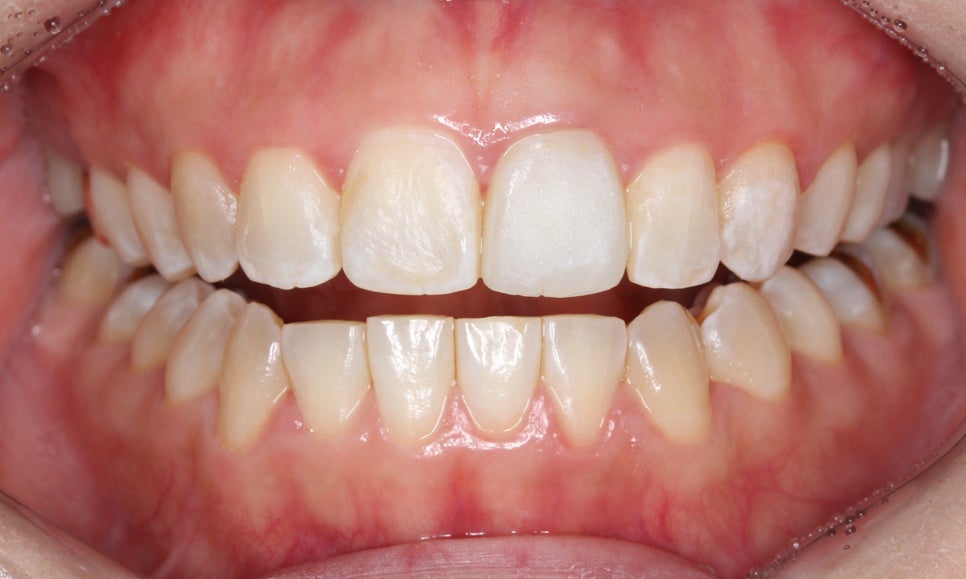

송곳니교정 전 전치부의 overjet 사진을 확인해보면

상악 중절치가 약간 돌출되어 있는 것을 확인할 수 있는데요,

아랫니도 미세하게 crowding이 발견되어 송곳니의

덧니 증상을 해결하면서 전치부 치열을

가지런하게 만들어야 할 것으로 보입니다.

overbite 사진에서도 과개교합이나

절단교합 증상이 나타나지 않고

바르게 교합되는 모습인데요,

측면에서 본 overjet 사진도

상악의 돌출감 없이 전치부가 교정된 모습입니다.